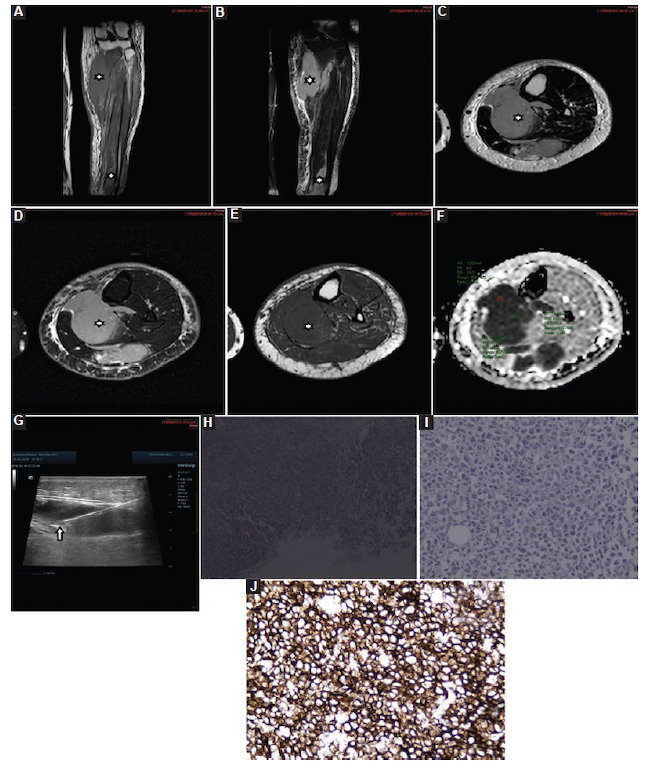

Metástasis: 24 pacientes presentaron metástasis, con una media de CDA de 0,88 ± 0,14 × 10−3 mm2/s (0,50-1,20) (Fig. 13), de las cuales fueron ocho de mama, cuatro de pulmón, tres de próstata, tres renales, dos gástricas, dos de ovario, una de vejiga y un melanoma.

Sarcomas: fueron 19 casos, con un valor medio de CDA de 1,33 ± 0,57 × 10−3 mm2/s (0,70-2,60) (Fig. 14), de los cuales fueron ocho sinoviales, cuatro fusocelulares, tres fibromixoides, dos pleomórficos y dos epitelioides.

Linfomas: fueron siete casos, con un valor medio de CDA de 0,69 ± 0,19 × 10−3 mm2/s (0,50-1,00) (Fig. 15), de los cuales fueron cinco linfomas B, un linfoma del manto y un linfoma cutáneo.

Condrosarcomas: fueron seis casos, con un valor medio de CDA de 0,90 ± 0,06 × 10−3 mm2/s (0,801,00) (Fig. 16), de los cuales fueron tres en el húmero, dos en el fémur y uno en la pelvis.

Sarcoma de Ewing: fueron cuatro casos, con un valor medio de CDA de 0,75 ± 0,19 × 10−3 mm2/s (0,500,90) (Fig. 17), de los cuales fueron dos en el fémur, uno en la pelvis y uno en la pierna (extraóseo).